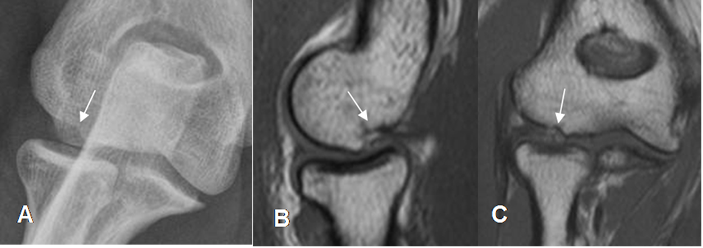

Existen 2 variantes normales, que no deben confundirse con patología en la RM. El seudodefecto del capitel y el seudodefecto del surco troclear. (8).

El seudodefecto del capitel se observa en la parte externa. Se valora en cortes axiales y debe tener bordes lisos, sin alteración en la señal de intensidad. Debe diferenciarse de fracturas, lesiones osteocondrales y quistes. (Fig 7 y 8).

Fig 7. Seudodefecto del Capitel.

A: Rx AP. B: RM sagital en T1 y C: RM coronal en T1.